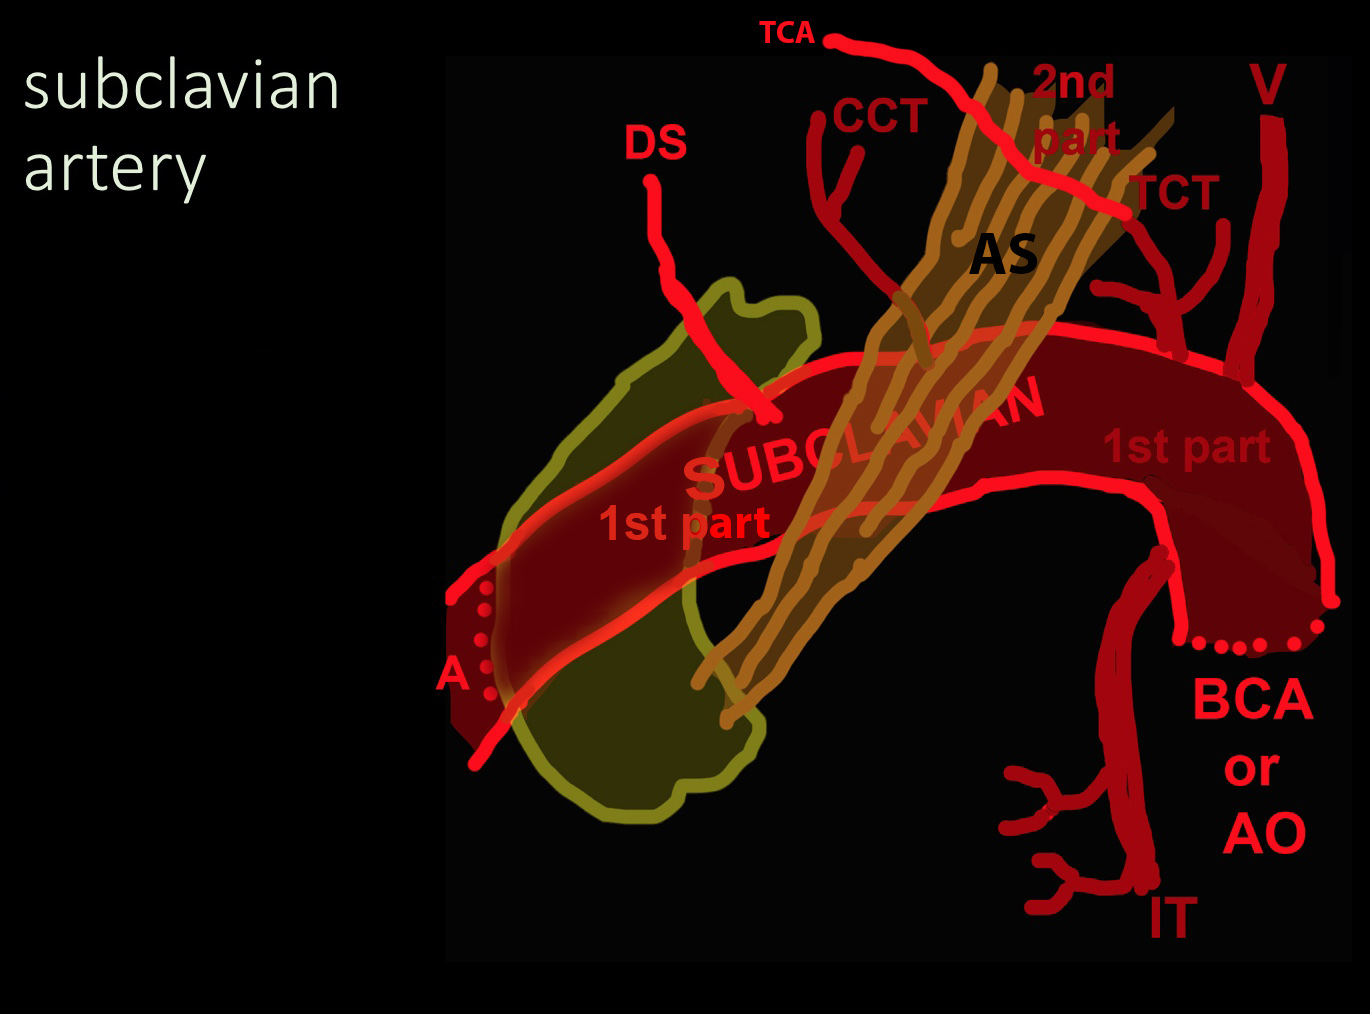

◂Breast Anatomy